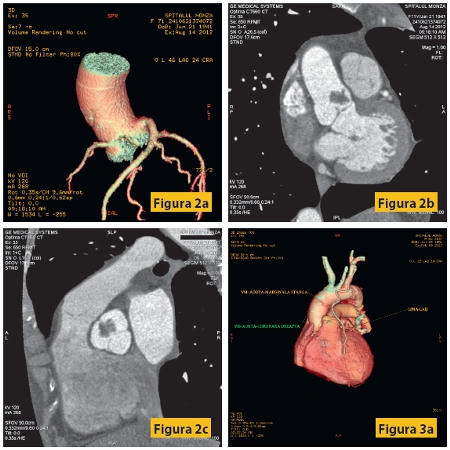

Figura 2: Pacient F, 71 ani, cunoscută cu proces expansiv de valvă aortică, cu anevrism septal interatrial permeabil, HTA stadiul II. Examinarea angiocoronaro-CT efectuată înaintea intervenţiei chirurgicale arată o circulaţie coronariană cu dominanţă stânga, fără stenoze semnificativă la nivelul arterelor coronare, precum şi procesul expansiv de la nivelul valvei (defect de umplere cu contururi neregulate, cu dimensiuni maxime de 16/13 mm, localizat la nivelul valvei aortice cu infiltrarea cuspei drepte).Examenul histopatologic a stabilit diagnosticul de fibroelastom.

Figura 3: Pacient M, 60 ani, cunoscut cu by-pass aortocoronarian, cu dureri anginoase reapărute în ultimile 4 luni, cu multipli factori de risc cardio-vasculari: diabet zaharat, hipertensiune arterială, dislipidemie. Examinarea coronarografică nu poate preciza cu exactitate permeabilitatea graftului cu artera marginală stânga, care apare opacifiat, cel mai probabil prin umplere retrogradă.

La examenul angiocoronaro-CT se evidenţiază graft LIMA-LAD (artera marginală inferioară stângă - artera descendentă anterioară stângă) permeabil, GRAFT-AORTĂ-MARGINALĂ STÂNGA trombozat, VSI-AORTĂ-CORONARĂ DREAPTA bont închis la nivelul aortei, precum şi un stent patent la nivelul ramului intermediar.